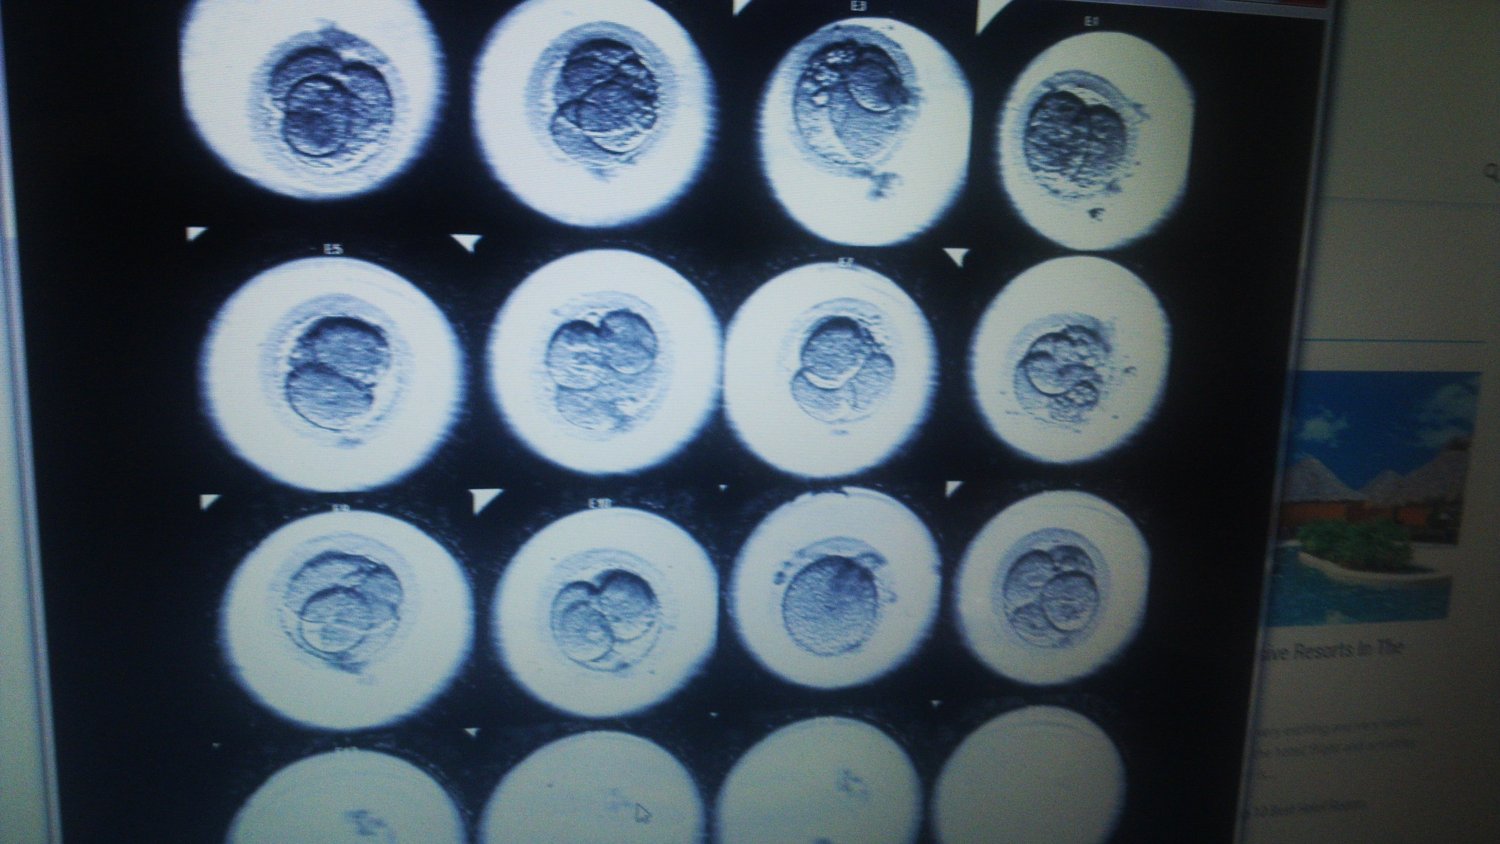

Te na zdjęciu to blastocysty. A zdjęcie zrobiłam oglądając film.

Ostatnie pięć dni kamera śledziła zarodki w szalkach, które, jak pamiętam z chemii, nazywają się szalkami Petriego. A może miniszalkami lub mikroszalkami, bo komórka nie jest taka duża.

Dr R pokazywał mi je z zachwytem w oczach: "My też tak naprawdę nie widzimy tego, jak się dzielą. Owszem, co rano się do nich zagląda i wyglądają inaczej, ale nigdy nie widzi się całego procesu" - i pokazał (chyba) bruzdę zarodkową. "Teraz oby była pani w ciąży".